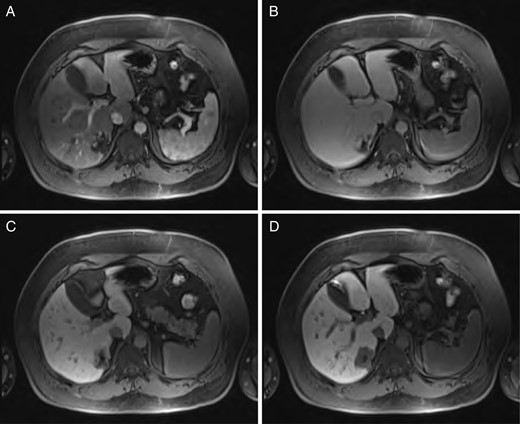

Sequential MRI imaging of HSFT: (A) T1 arterial phase, (B) T1 60-s delay phase, (C) T1 postcontrast phase and (D) T1 hepatographic phase.

A 40-year-old male underwent computed tomography (CT) scan of the chest for atypical chest pain, which revealed an indeterminate 3-cm lesion in the right liver. He subsequently underwent triple-phase CT, which revealed two separate lesions: a 4.3 × 5.3-cm discrete mass in the left liver (Segment 2) and a 2.3 × 3.7-cm lobular, partially exophytic hypodense lesion in the right liver (Segment 6). On the delayed phase, the periphery of the right posterior hepatic mass was isodense with the rest of the liver parenchyma, but the central portion remained hypodense. Based on these findings, the right-sided lesion was felt to be a hemangioma, but the findings were still inconclusive regarding the left-sided lesion. Magnetic resonance imaging (MRI) was performed with intravenous gadoxetic acid, a hepatocyte-specific contrast agent. The lesion in Segment 2 was hypointense on precontrast T1, hyperintense on T2-weighted images, and showed avid enhancement on the arterial and portal venous phases. There was a delayed washout on the hepatographic phase. Although nonspecific, this was felt to be most consistent with an adenoma. The right-sided lesion showed postcontrast gradual enhancement with centripetal fill-in, reinforcing the diagnosis of hemangioma (Figs 1 and 2).